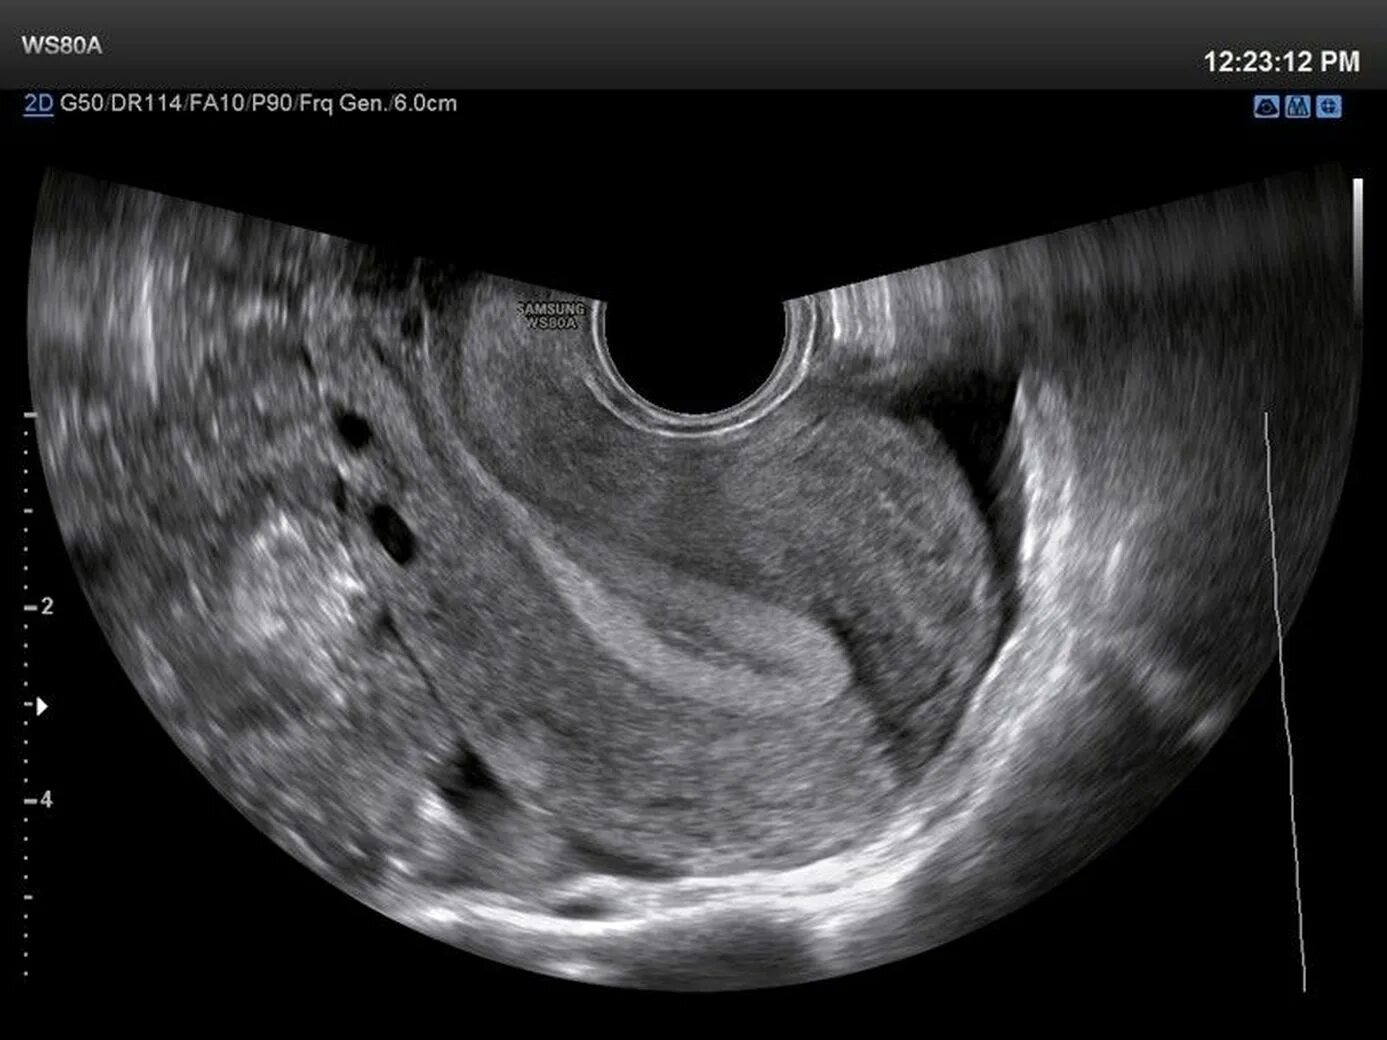

Ребенок исчез во время узи как называется